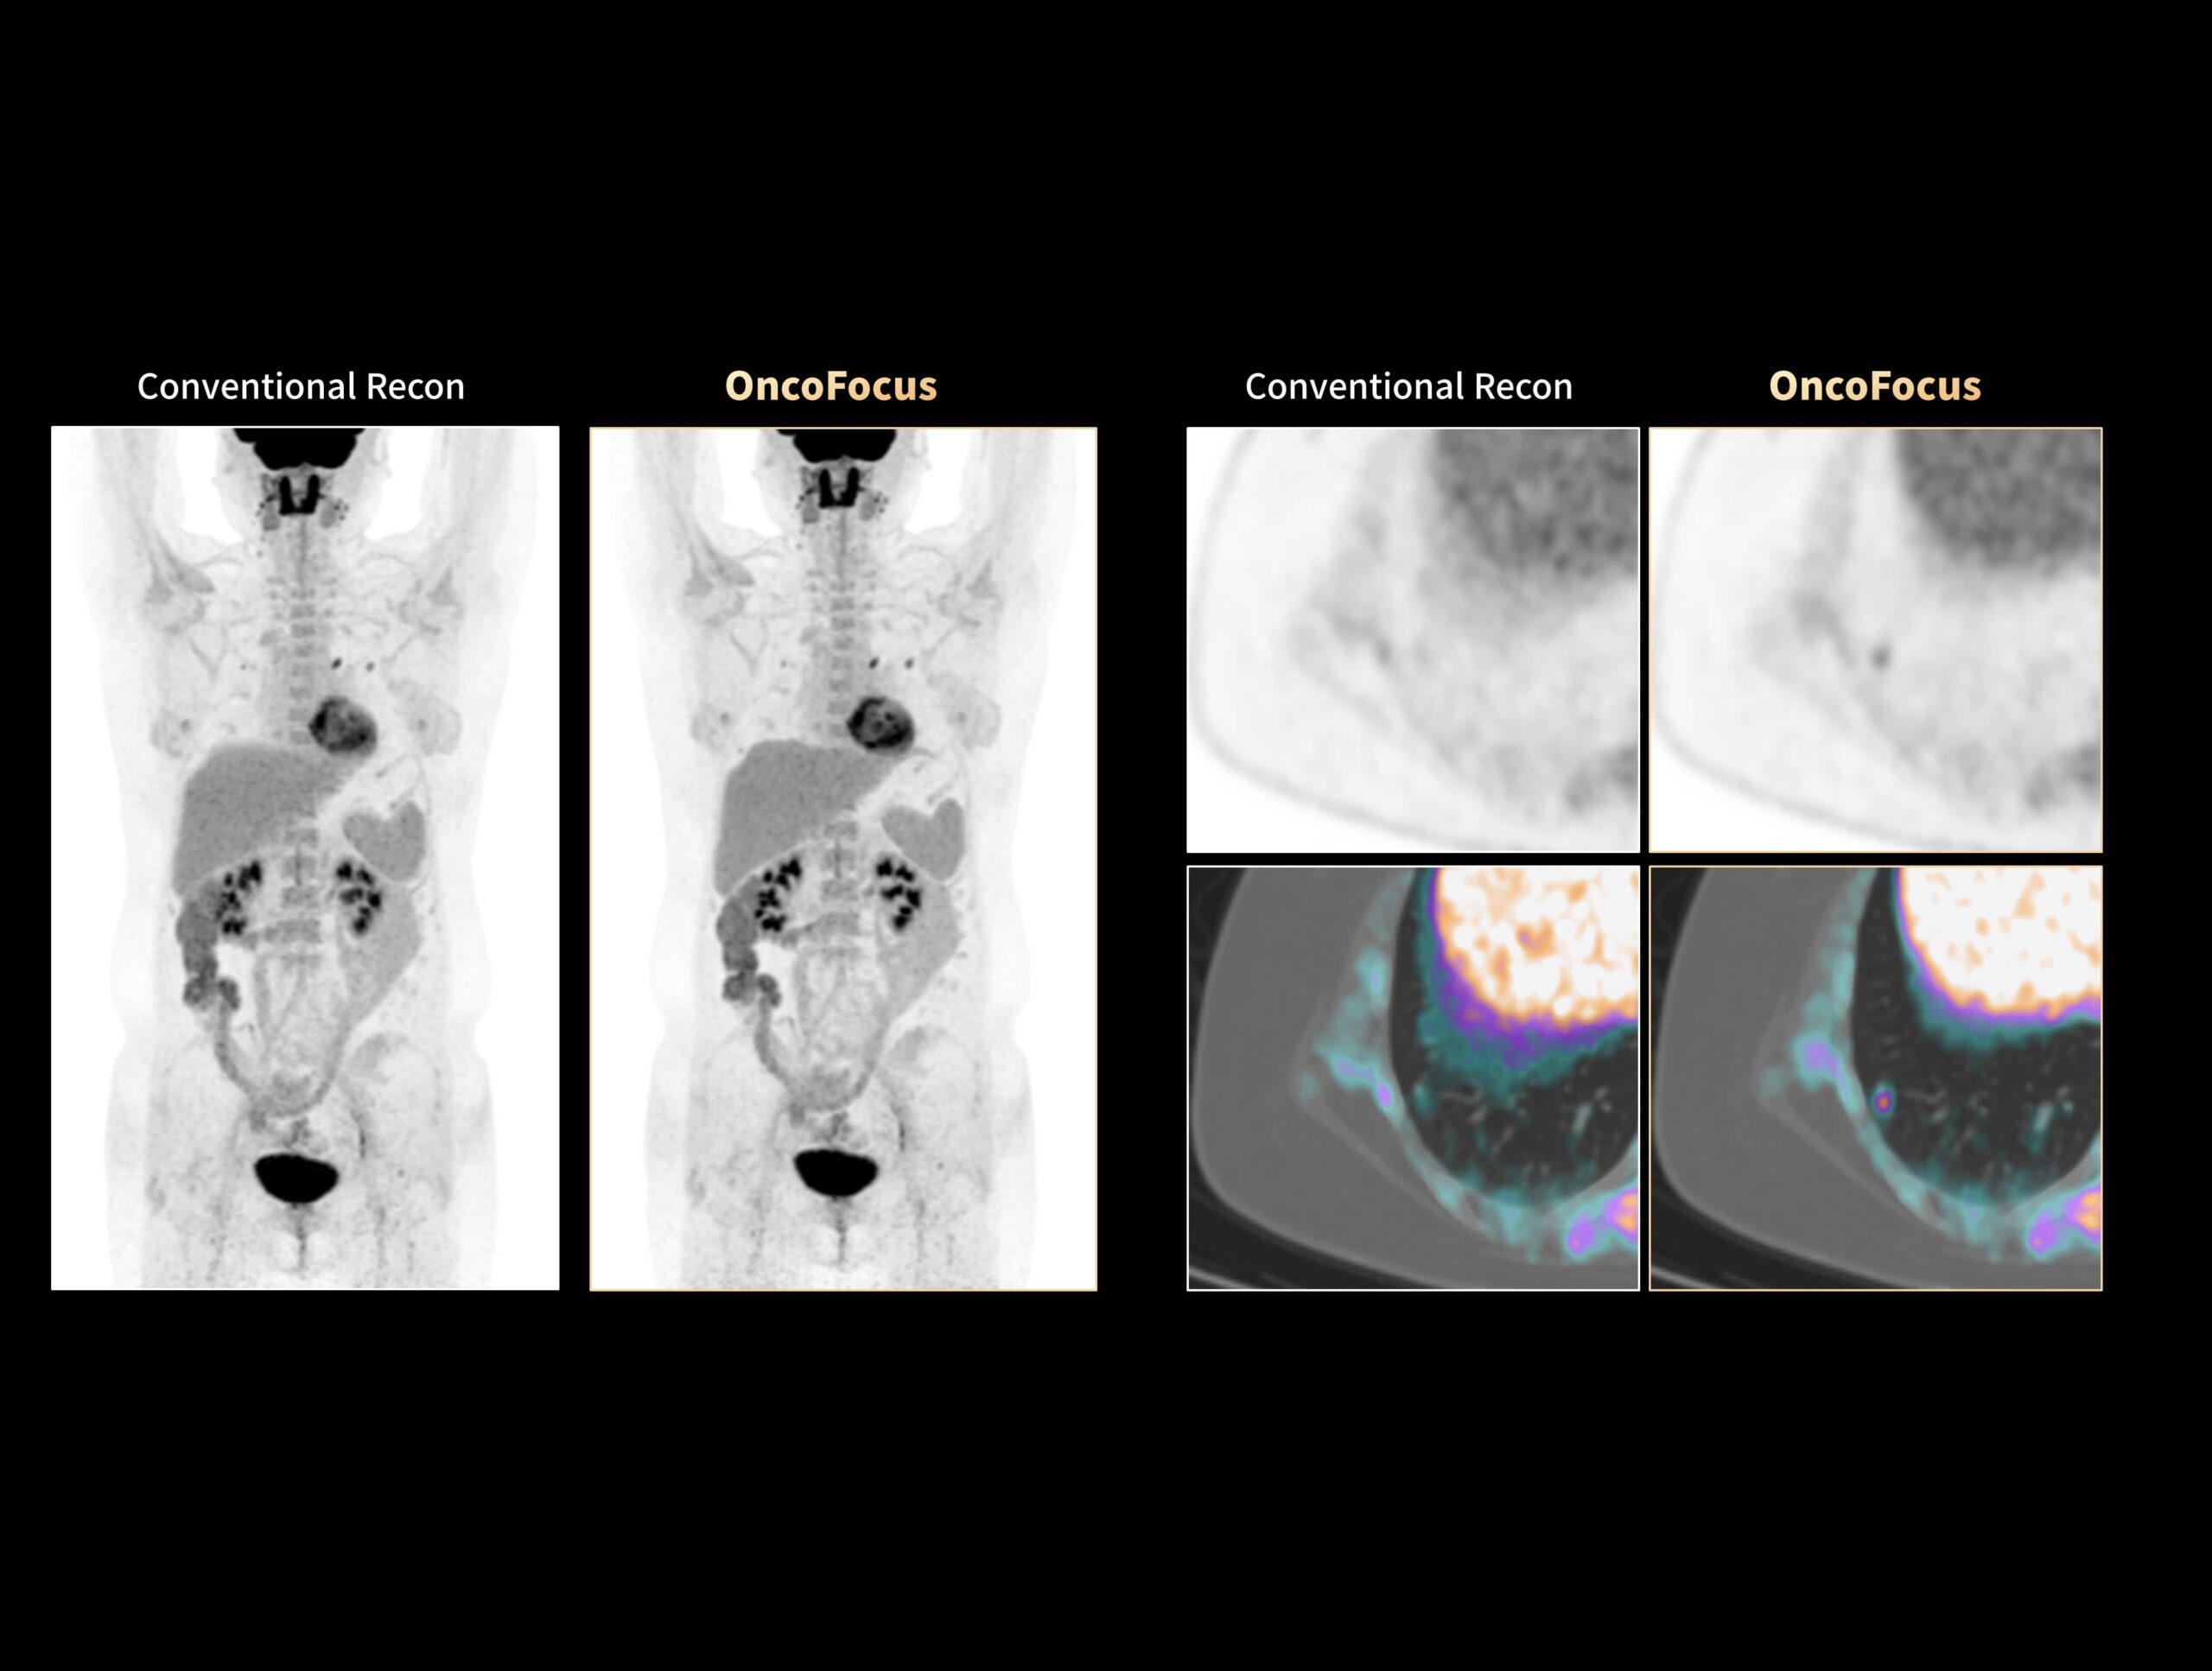

OncoFocus evidențiază clar leziunile hepatice și gastrice

OncoFocus evidențiază clar nodulii pulmonari subcentimetrici

Cancerul pulmonar cu metastaze hepatice greu vizibile poate fi detectat cu OncoFocus

Leziunile nediagnosticate ale osteosarcomului cu metastaze hepatice și pulmonare pot fi vizualizate cu OncoFocus